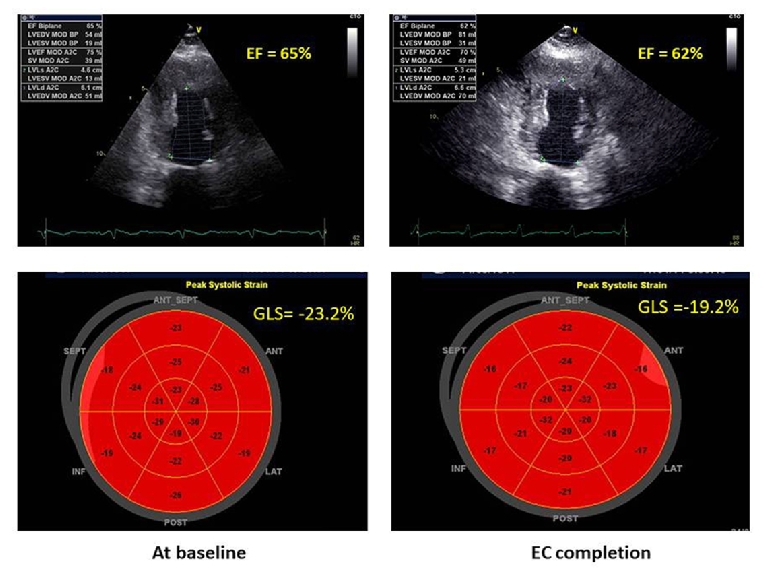

A multi-modality imaging approach to pericardial damage in cancer patients should be performed according to the EACVI position paper on myocardial and pericardial diseases [13]. Echocardiography is the first-line cardiac imaging for the diagnosis of radiotherapy-induced pericarditis. Figure 2 illustrates a significant pericardial thickening (>2 mm) two years after the end of radiotherapy for lymphoma. However, although pericardial thickness is currently considered a main criterion for diagnosing constrictive pericarditis, the range of pericardial thicknesses is highly variable (1–17 mm, mean 4 mm), with up to 20% of patients showing a normal thickness (<2 mm). Cardiac tamponade may be suggested by large fluid accumulation, compression of the cardiac cavities, and right-sided venous congestion. Serial echocardiographic examinations are helpful in patients affected by pericardial effusion or constrictive pericarditis but are less useful for identifying pericardial thickening and calcifications. CMR and cardiac CT, also using LGE (pericardial enhancement suggests residual pericardial inflammation), are more sensitive in detecting specific anatomical abnormalities of the pericardium. End-stage chronic constrictive pericarditis cannot show pericardial LGE on CMR, whereas pericardial enhancement is demonstrative of residual inflammation.

Figure 2. 2D echocardiographic subcostal view showing a significant RV pericardial thickening (>2 mm at the RV free wall) in a patient with lymphoma who had undergone mediastinal radiotherapy two years before the echo examination.